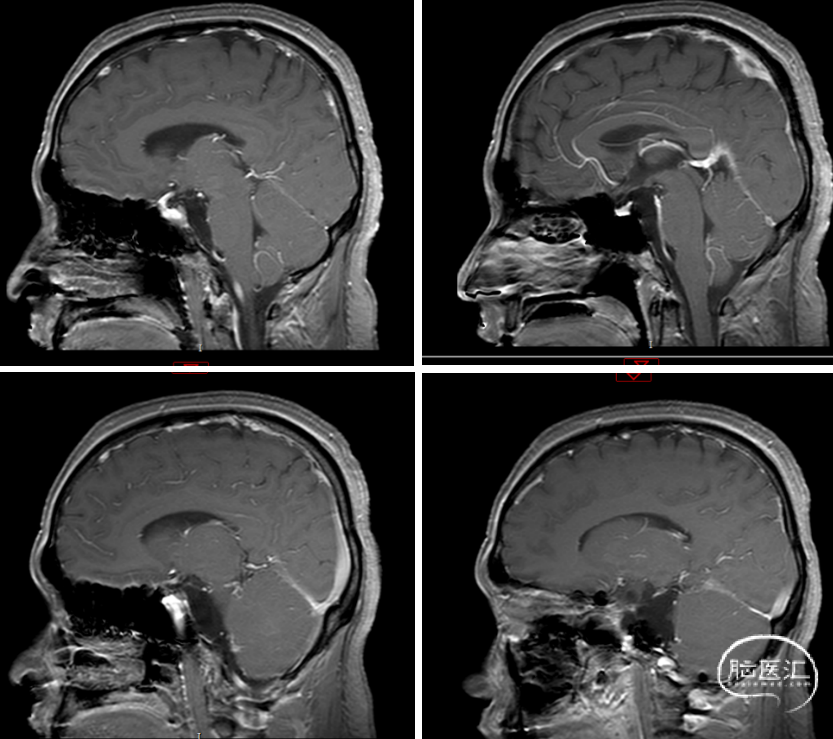

术后MRI